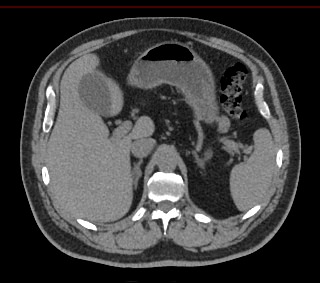

Одним из наиболее информативных методов диагностики заболеваний надпочечников является мультиспиральная компьютерная томография. МСКТ надпочечников относится к лучевым методам исследования, то есть для получения послойного изображения структуры органа используется проникающая способность рентгеновских лучей.

В клинике «Доступная медицина» мультиспиральная КТ надпочечников выполняется на современном 128-срезовом томографе экспертного класса TOSHIBA AQUILION CXL, который производит множество послойных снимков за несколько секунд. Быстрота исследования обеспечивает пониженный уровень лучевой нагрузки на пациента, а благодаря инновационным компьютерным программам томограф создает трехмерные модели органа, позволяющие оценить структуру надпочечников и окружающие ткани.

Кроме нативной компьютерной томографии МСКТ надпочечников проводится с применением рентгеноконтрастного вещества на основе йода. Контраст вводится пациенту внутривенно и усиливает визуализацию новообразований на фоне неизмененных тканей.

Контрастирование позволяет, в первую очередь, обнаружить опухоли минимальных размеров, что особенно важно при онкологических процессах для назначения своевременного лечения.